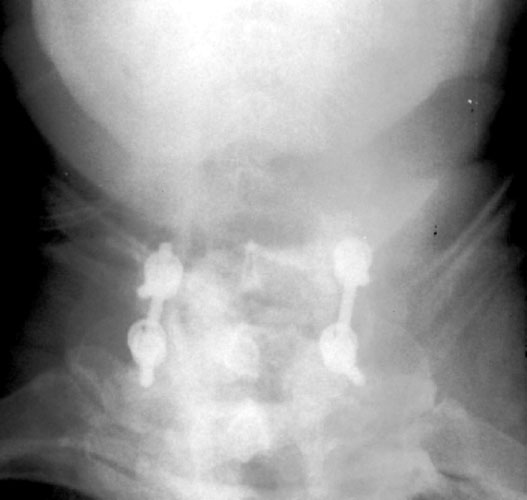

Radiographs obtained 5 months post-operatively demonstrate normal C6-7 fusion without evidence of hardware failure.